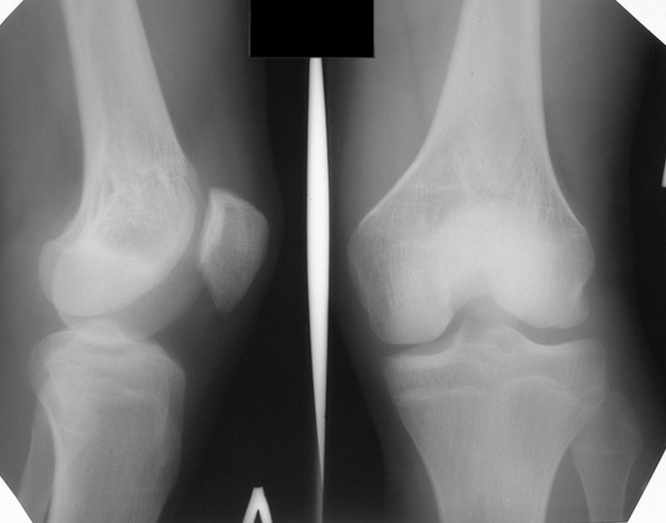

Больной Н., мужчина 18 лет с укорочением бедра и рекурвацией коленного

сустава.